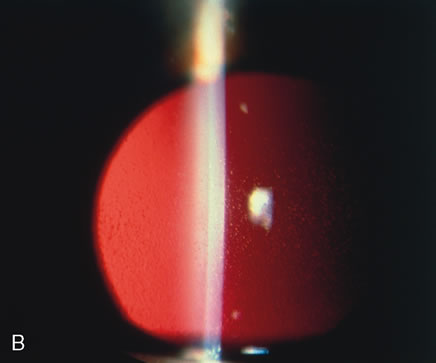

Syphilis is a venereal disease caused by the spirochete Treponema pallidum, which primarily affects the central nervous and cardiovascular systems. During the past decade, syphilis has again become more common. Often syphilis is found in patients who also have acquired immune deficiency syndrome (AIDS).101 The organism is highly infectious but of low virulence, resulting in long periods of latency and prolonged viability unless specifically treated. Many of the tissue effects of syphilis are due to host immune response, such as mononuclear cell infiltrates, proliferative vascular changes, and occasionally granuloma formation. The cornea often is not affected by acquired syphilis but is commonly affected by congenital syphilis (Fig. 12). Infection of the fetus occurs transplacentally after the fifth month of gestation. Diffuse fibrosis can compromise the function of any parenchymatous organ, including the lungs.

Fig. 12. Syphilis. A. Corneal ghost vessels as viewed by fundus reflex in a patient with congenital syphilis. B. Slit lamp appearance of interstitial keratitis. C. A blood vessel (arrow) present anterior to Descemet's membrane (d). D. Retrocorneal ridges of Descemet's membrane form refractile, branching straight lines. E. A multilayered strand extends from a thickened Descemet's membrane into the anterior chamber.(Courtesy of SEI Photoarchives.) (B Courtesy of Dr. W. C. Prayer; D and E from Waring GO, Font RL, Rodrigues MM et al: Alterations of Descemet's membrane in interstitial keratitis. Am J Ophthalmol 81:773, 1976.)

The cornea is particularly involved in a late-occurring form of congenital syphilis, which also causes periostitis, saber chins, saddle nose deformity, and tooth deformities (Hutchinson's teeth).102 Congenital syphilis presents between the ages of 5 and 10 years with an intense keratitis that may last for several months and may reduce visual acuity to counting fingers or seeing hand movements.103 Fortunately, usually a significant regression occurs with a parallel improvement of visual acuity, often in the range of 20/40 to 20/60. The acquired form of interstitial keratitis tends to be unilateral (it may even be sectorial) and tends to occur during the third or fourth decade of life as an expression of tertiary syphilis.

Histologically, the cornea shows edema and infiltration by lymphocytes and plasma cells. Vessels usually are seen in the deep portion of the cornea, just anterior to Descemet's membrane. Although the edema and inflammation of the corneal stroma resolves, the deep vessels persist in the form of ghost vessels. Often blood flow is minimal but persistent through the vessels, even though they appear empty. Chronic interstitial inflammation causes alterations of Descemet's membrane that are characteristic of congenital syphilis and include linear guttae with ridges and even nests of transparent basement membrane material, which may project into the anterior chamber.104,105

The association with uveitis is frequent and occasionally may lead to significant synechia formation. It should be noted that in the anterior chamber, antigens to T. pallidum may be found.